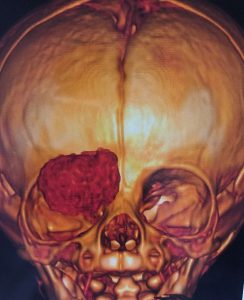

Tumores Orbitários

Os pacientes com TUMORES ORBITÁRIOS, benignos ou malignos, recebem de nossa equipe uma atenção especial. É um campo da Oculoplástica que nos dedicamos com afinco. Acometem crianças e adultos. São incomuns, mas quando aparecem podem colocar a visão em risco. Eventualmente se estendem para o sistema nervoso ou se espalham pelo corpo. Alguns são operáveis, outros são eliminados com radioterapia/quimioterapia. É preciso um estudo diagnóstico minucioso, uma estratégia cirúrgica bem traçada, além de um suporte emocional adequado